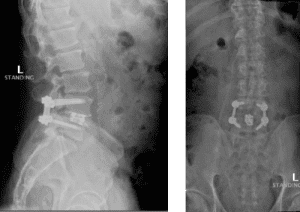

Image 3. Post-op x-rays that show L4/L5 transforaminal lumbar interbody fusion (TLIF). There was also removal the L2/L3 disc herniation but no need for instrumentation.

Dr. Imani was able to decompress both the L2/L3 level (with disc herniation removal) and the L4/L5 level. Additionally, L4/L5 level was fused using titanium screw and an expandable interbody cage. This was performed with a very small incision. The patient has no more leg pain and back pain, and is doing very well!